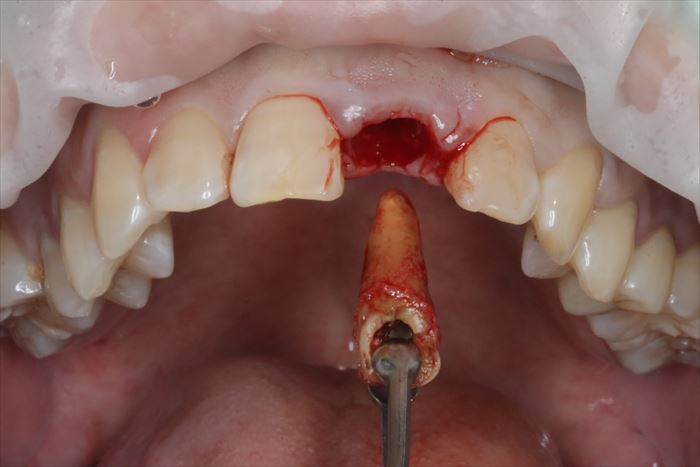

では、いよいよ仮歯を外して抜歯即時インプラント埋入オペのスタートです。

歯肉が歯根の上面をカバーするように増殖して覆い隠しています。

増殖して覆い隠している歯肉は正常像ではありませんので必要最小限切除して抜歯します。

抜歯時には極力周囲の歯槽骨にダメージを与えないように(非侵襲的に)慎重に抜歯します。